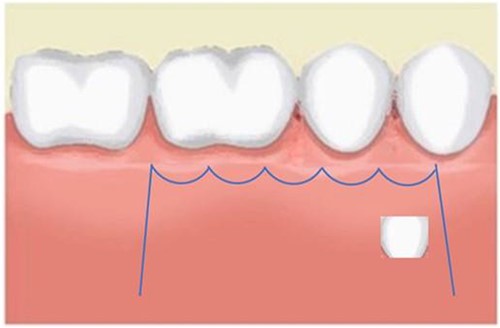

A Neumann full-thickness buccal flap was utilized to remove these during the course of orthodontic treatment. The shortcoming of the buccal surgical removal approach is that although it is better for visualization, it poses a high risk of trauma to the adjacent teeth or nerves [4, 5]. As the premolar was being removed on the right side, there was a fracture of the root apex (Fig. 2). On the left side, the premolar bud could be removed without any trauma to the adjacent tooth roots. After months of follow-up, there was normal bone formation, and no other symptoms were identified (Fig. 3).

Follow-up panoramic 1 week after removal of the supernumerary premolars.